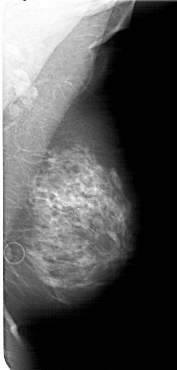

A_1632_1.LEFT_CC

LEFT_CC LINES 6811 PIXELS_PER_LINE 3016 BITS_PER_PIXEL 12 RESOLUTION 43.5 OVERLAY

FILE: A_1632_1.LEFT_CC.OVERLAY

TOTAL_ABNORMALITIES 1

ABNORMALITY 1

LESION_TYPE CALCIFICATION TYPE PLEOMORPHIC DISTRIBUTION CLUSTERED

ASSESSMENT 4

SUBTLETY 2

PATHOLOGY BENIGN

TOTAL_OUTLINES 1

BOUNDARY